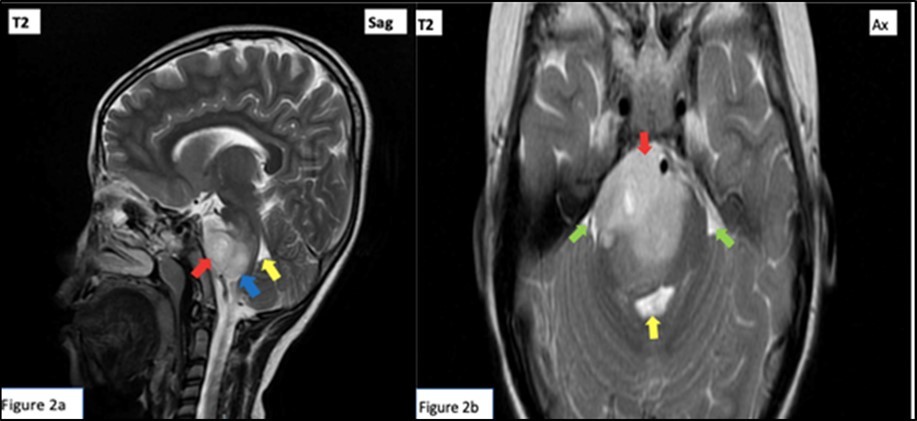

Cranial MRI with contrast was done, revealing a right pontine mass with features of glioma typical of a diffuse intrinsic type exhibiting T1 hypointensities, T2 hyperintensities involving majority of the pons with associated signal changes.4Hence, patient was diagnosed with Raymond Syndrome probably secondary to a presumed pontine glioma, Right. Patient was referred for evaluation and co-management with Neurosurgery and Pediatric Neurology services. Patient subsequently underwent radiotherapy.

Red arrow: Peripherally enhancing 2.6 x 4.1 x 2.8 cm lobulated mass centered on the right tegmentum of the pons, exhibiting hyperintensity (and hypointensity in T1 weighted images, not shown). Mass renders the pons enlarged and displaces the rest of the pontine parenchyma peripherally. Green arrow: Effacement of bilateral cerebellopontine angle. Yellow arrow: Mild compression on the 4th ventricle. Blue arrow: Small similar looking lesions at medulla oblongata. (Figure 1, Figure 2)

Figure 2.T2 Weighted cranial magnetic resonance imaging sagittal (a) and axial (b) cuts.